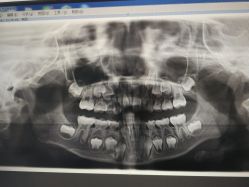

• 睿宝儿科·眼科·口腔(静安大悦城门诊部)

• -睿宝儿科·眼科·口腔(静安大悦城门诊部)

• 门诊部-睿宝儿科·眼科·口腔(静安大悦城门诊部)

• 门面-睿宝儿科·眼科·口腔(静安大悦城门诊部)